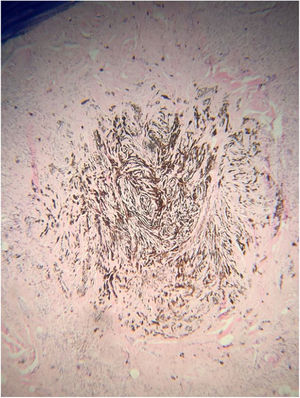

A análise histopatológica da lesão evidenciou proliferação difusa de melanócitos dispostos em ninhos de tamanhos e formas regulares na derme papilar e em cordões na derme reticular que circundava estruturas anexiais a par de área focal onde predominavam melanócitos de padrão dendrítico com abundante pigmento melânico no citoplasma. Além de fibroplasia do colágeno, reação granulomatosa tipo corpo estranho em torno da haste de pelo livre observaram-se formações ósseas homogêneas compatíveis com ossificação cutânea. O diagnóstico histológico foi de osteonevo de Nanta em nevo combinado – intradérmico e azul (figs. 3, 4 e 5). O estudo imuno‐histoquímico confirmou a natureza melanocítica da lesão, com positividade para os marcadores S‐100, MART‐1, gp100.

Na análise histológica nota‐se geralmente a ossificação como pequenas ilhas de osso compacto lamelar ou amorfo na base da lesão melanocítica,3 na derme reticular próximo a folículos pilosos,4,10 pode ser com foco único ou múltiplos.3 Em alguns casos, osso trabecular com medula óssea e adipócitos podem estar presentes.3 O achado de infiltrado mononuclear, granuloma de corpo estranho ou granulomas mistos é frequente.2

No caso relatado houve a caracterização de nevo combinado – nevo melanocítico intradérmico e nevo azul – associado à presença de tecido ósseo homogêneo na derme reticular próximo a folículos pilosos e reação granulomatosa tipo corpo estranho. Não foram identificados relatos na literatura de ossificação de nevo combinado, esta provavelmente é a primeira descrição da associação.